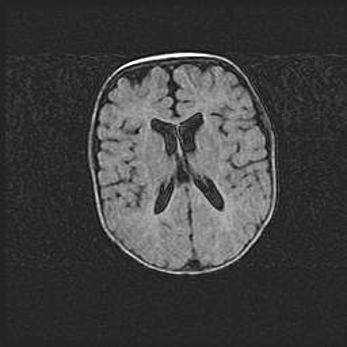

Множественные кисты обоих полушарий головного мозга, наибольшая из них в правой затылочной области. Ассиметричная атрофическая гидроцефалия.

Возраст: 7 месяцев

Вес: 5660 г

Пол: мужской

Окружность головы: 41,5 см

Срок гестации: 28-29 недель

Кисты головного мозга развиваются в результате многоочаговых некрозов вещества мозга и возникают вследствие перенесенной перинатальной инфекции, менингитов, энцефалитов, асфиксии, родовой травмы, расстройств мозгового кровообращения различного генеза. Образованию кист в веществе головного мозга плодов и новорожденных способствуют такие факторы, как высокое содержание в нем воды, недостаточная (или отсутствие) миелинизация и слабая астроглиальная реакция на повреждение.

Кисты могут сочетаться с гидроцефалией и другими поражениями головного мозга.